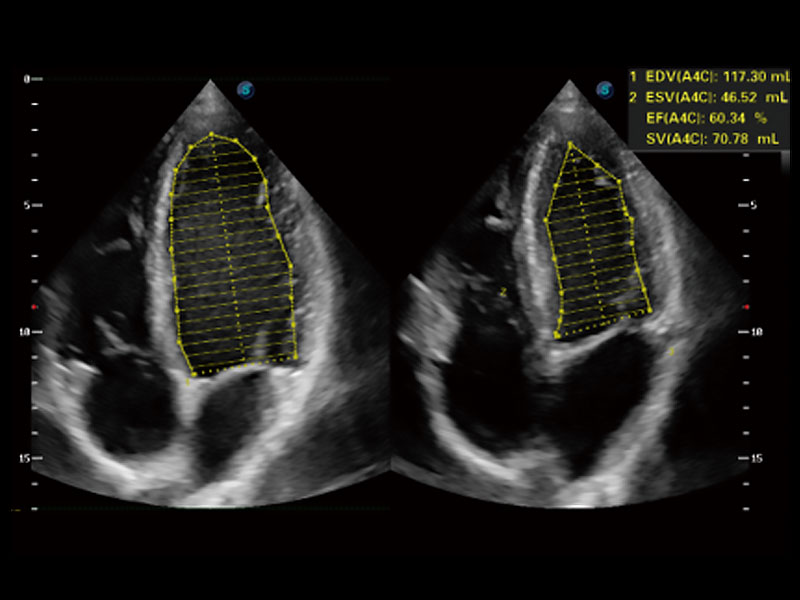

能夠基于左心室壁追蹤和辛普森法,自動計算射血分數(shù),支持多個可移動點描跡,與手動測量相比,極大節(jié)省了動物醫(yī)生的時間和精力。